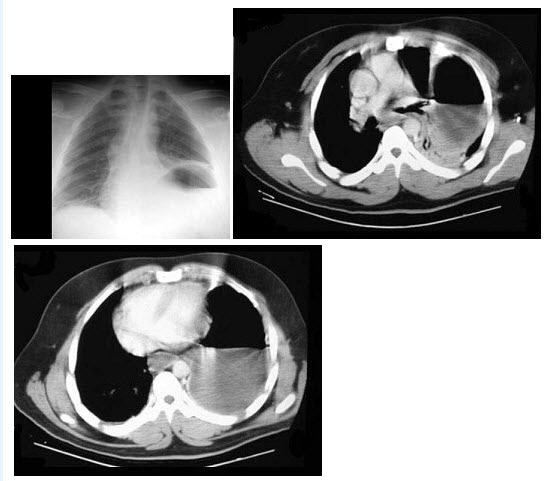

男,55岁。突发胸痛就诊。胸部动脉CT造影如下图,可诊断为()

A.主动脉瘤

B.主动脉夹层(DeBakeyⅠ型)

C.主动脉夹层(DeBakeyⅡ型)

D.主动脉夹层(DeBakeyⅢ型)

E.主动脉血栓

点击查看答案

本题答案:微信扫下方二维码即可打包下载完整带答案解析版《★放射医学(医学高级)》或《放射医学(医学高级):CT》题库

241、单项选择题

男,35岁,因车祸入院,呼吸困难、发绀、上腹痛,结合胸片和CT,最可能的诊断是()

A.膈疝

B.胸腔积液

C.膈膨升

D.膈麻痹

E.液气胸

点击查看答案

本题答案:微信扫下方二维码即可打包下载完整带答案解析版《★放射医学(医学高级)》或《放射医学(医学高级):CT》题库